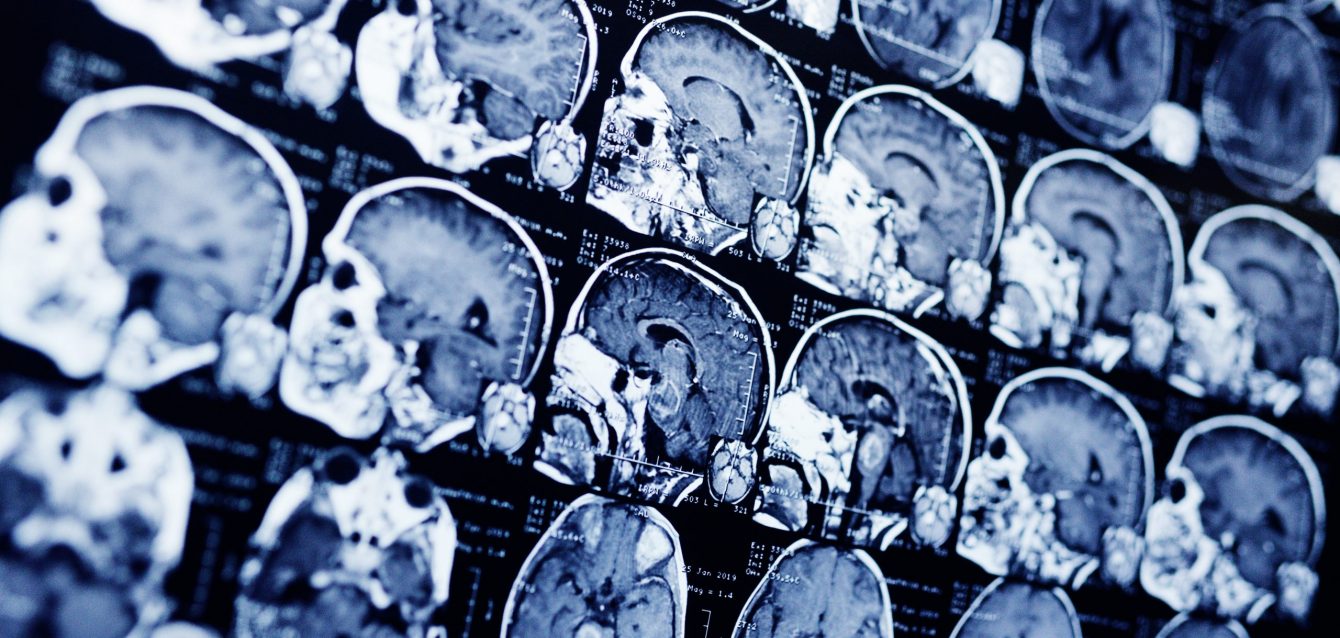

Tumores cerebrales infantiles La medicina de precisión, en la que el diagnóstico y los tratamientos se adaptan a las susceptibilidades genéticas de cada tipo de cáncer, puede desempeñar un papel importante en el tratamiento de los niños con tumores cerebrales, según sugiere un estudio realizado por investigadores del Dana-Farber/Boston Children’s Cancer...

Científicos de la Universidad de East Anglia han demostrado cómo el principal ingrediente psicoactivo del cannabis podría reducir el crecimiento tumoral en pacientes con cáncer. Las investigaciones revelan la existencia de plataformas de señalización hasta ahora desconocidas que son responsables del éxito de la droga en la reducción de tumores...